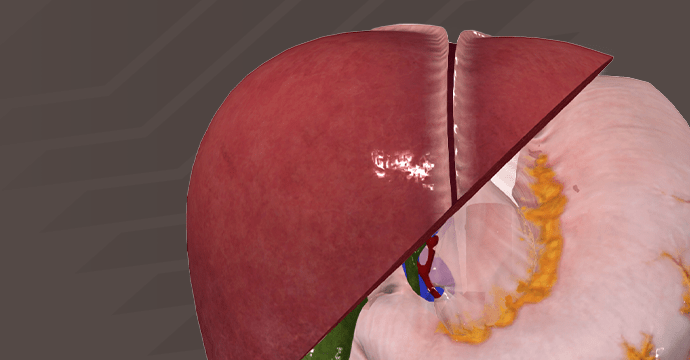

Take your understanding of human anatomy to the next level. Our comprehensive resources combine detailed information and stunning illustrations!

Enhance your studies for a truly dynamic learning experience. Explore interactive anatomy models from Complete Anatomy. Start mastering anatomy today with our free anatomy flashcards designed for quick review on the go.